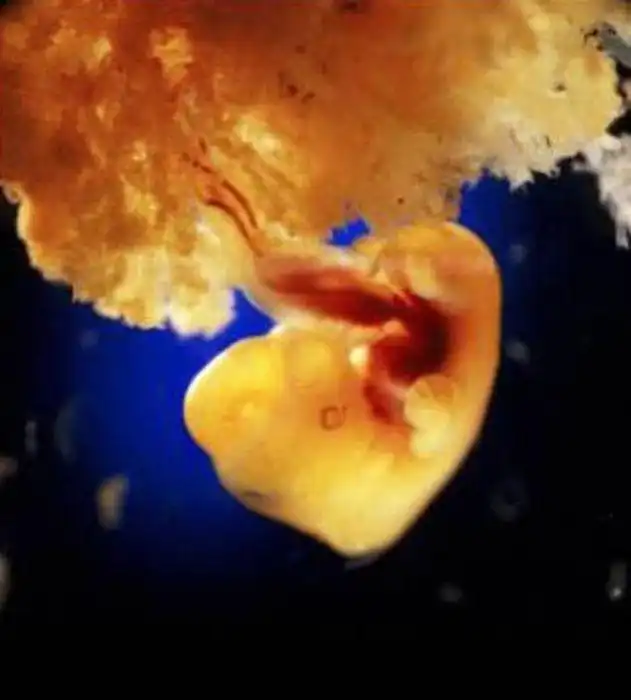

40 дней. Наружные клетки зародыша срослись с рыхлой поверхностью матки и образуют плаценту, или детское место. Это губчатый кусок плоти служит человеку в первые девять месяцев его жизни и легкими, и желудком, и печенью, и почкой...